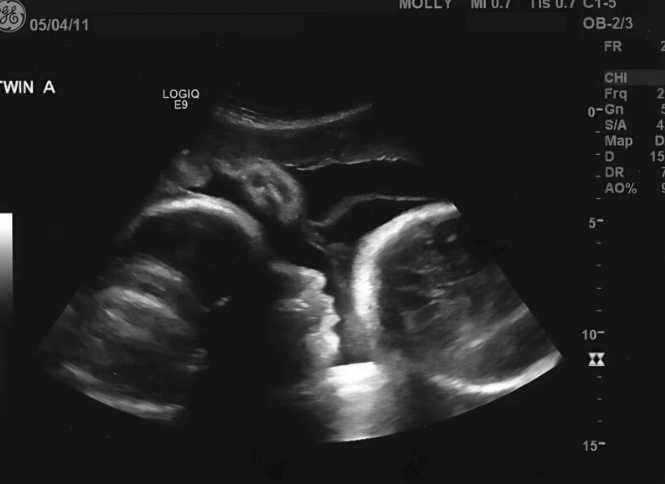

Kada je napokon odlučila da ode kod ginekologa, verovala je da je vreme da sazna kako će se poroditi. Prošlo je devet meseci, prema njenim proračunima, i bila je sigurna da će uskoro roditi. Kada je lekar video njen uzrast, bio je zabrinut, ali ništa nije mogao da pretpostavi. Nakon nekoliko pregleda, lice lekara je postalo bledo. Na ekranu nije bilo bebe. Iako su testovi pokazali trudnoću, to nije bila stvarna trudnoća – bila je to posledica ozbiljnog medicinskog problema koji je uzrokovao da joj stomak raste.

- Iznenađenje lekara i istina koju Larisa nije želela da prihvati

- Nije bilo bebe, već ozbiljan medicinski problem